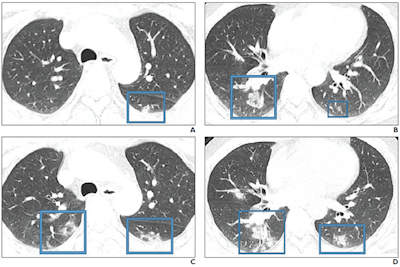

"An investigation of initial chest CT findings in 21 individuals with confirmed COVID-19 reported abnormal findings in 86% of patients, with a majority having bilateral lung involvement," the authors wrote.

"Although the imaging features [of COVID-19] closely resemble those of MERS and SARS, involvement of both lungs on initial imaging is more likely to be seen with COVID-19," the group wrote. "Initial chest imaging abnormalities in SARS and MERS are more frequently unilateral."

The three diseases share the following symptoms: fever, dyspnea, malaise, myalgia, and headache; all three also tend to show ground-glass opacity, consolidation, or both on imaging, while lymphadenopathy is not usually seen. Clinicians have been diagnosing COVID-19 in patients with these symptoms who recently traveled to China.